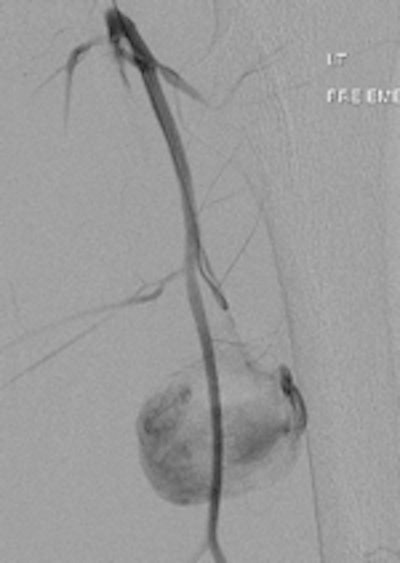

A 19-year-old male with delayed presentation following gunshot injury in the thigh. Left: T1 coronal MRI shows a large pseudoaneurysm in the upper thigh. Pre- (middle) and postembolization (right) angiographic images demonstrate successful treatment of the pseudoaneurysm.The two mechanisms of tissue injury that account for the majority of damage caused by a bullet are direct crushing of tissue by the projectile (causing a permanent cavity) and temporary cavitation, which stretches and tears surrounding tissues. Increased velocity, fragmentation, deformation, and rolling/spinning of the bullet will cause more damage by both these mechanisms, he pointed out.